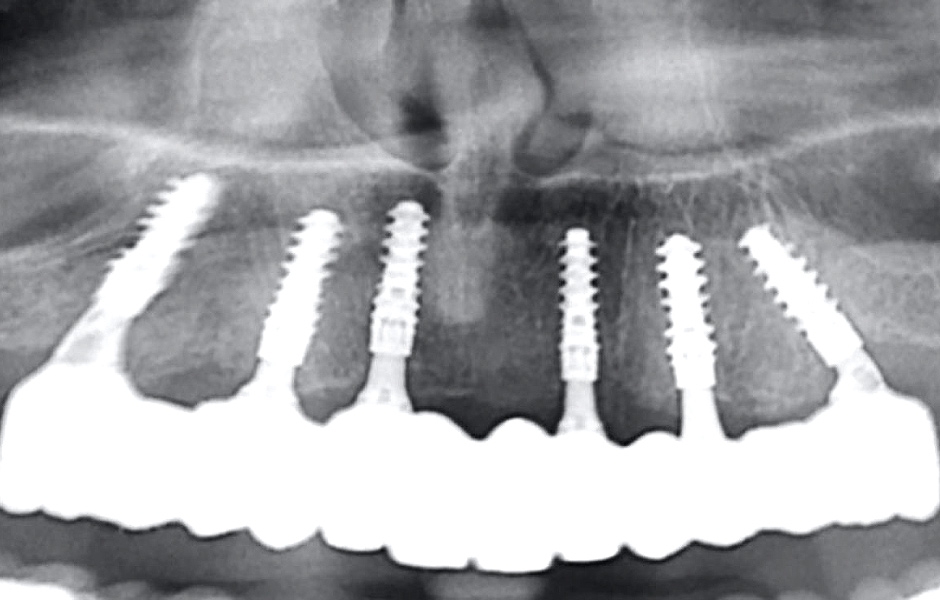

Definitivní náhrada byla nasazena a ověřena z hlediska estetiky, okluze a funkce (obr. 51–55). Panoramatický kontrolní snímek potvrdil, že všechny parametry protetického ošetření odpovídají očekávaným hodnotám (obr. 56).

Při kontrole po 18 měsících po dokončení ošetření bylo provedeno intraorální, extraorální a radiografické vyšetření. Nebyly zjištěny žádné patologické nálezy a výsledné parametry zůstaly stabilní (obr. 57–62).

Obr. 56